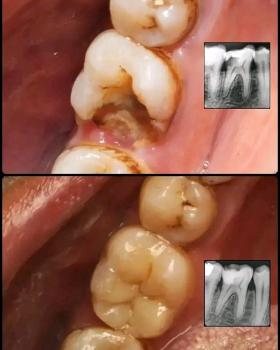

Fixed Bridge

A false tooth is anchored to the two adjacent healthy teeth, which are capped with crowns. This provides a fixed, non-removable solution and does not require surgery.